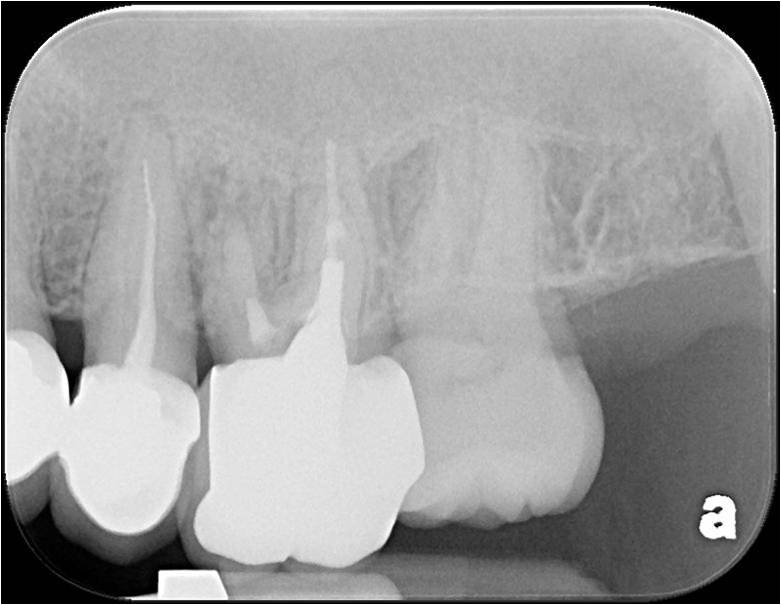

治療後X光再次檢查密合性